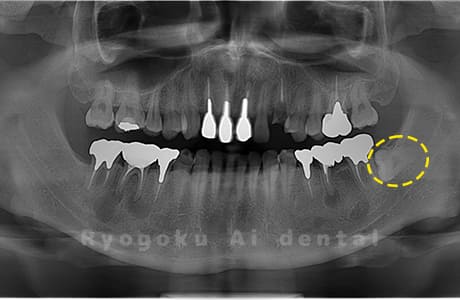

Case03

-

- 原因

- 上顎、下顎の親知らず

- 治療内容

- 上下4本の親知らずを抜歯したケースです。

<リスク・副作用>

手術後は痛み、腫れ、痺れなどの副作用が生じる場合があります。